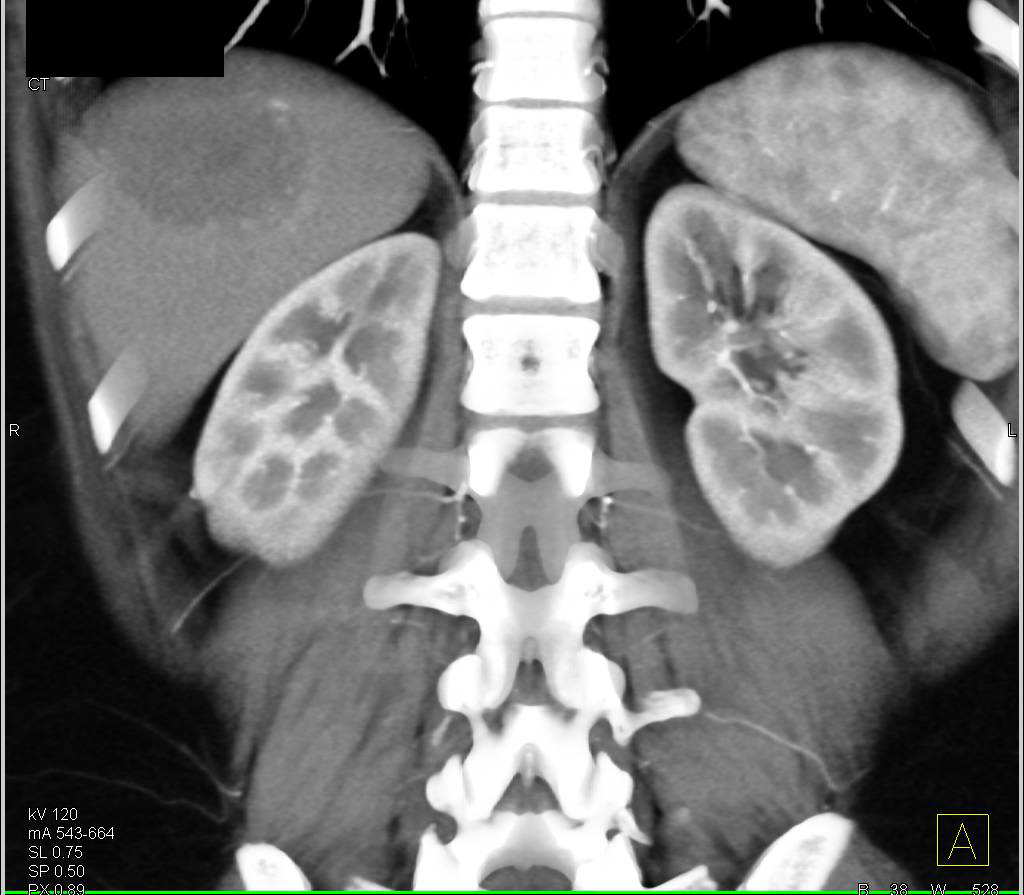

Atypical Hemangioma in the Right Lobe of the Liver